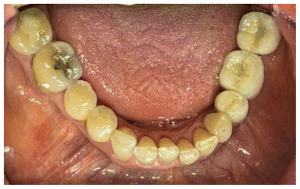

The first premolar due to the inclination had to be milled and a cemente Crown was used, the mollars were milled and scre retained (Figure 33).

The abutments were torqued to 30 Newtons. The premolar crown was cemented with Premier implant cement, and the screw access channels of the molar crowns were filled with resin (Figs. 34, 35).